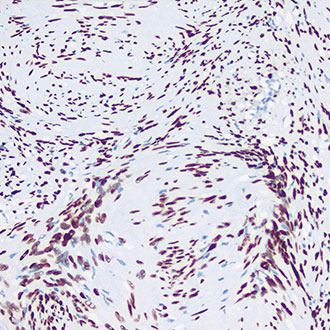

IHC

免疫组织化学(IHC)